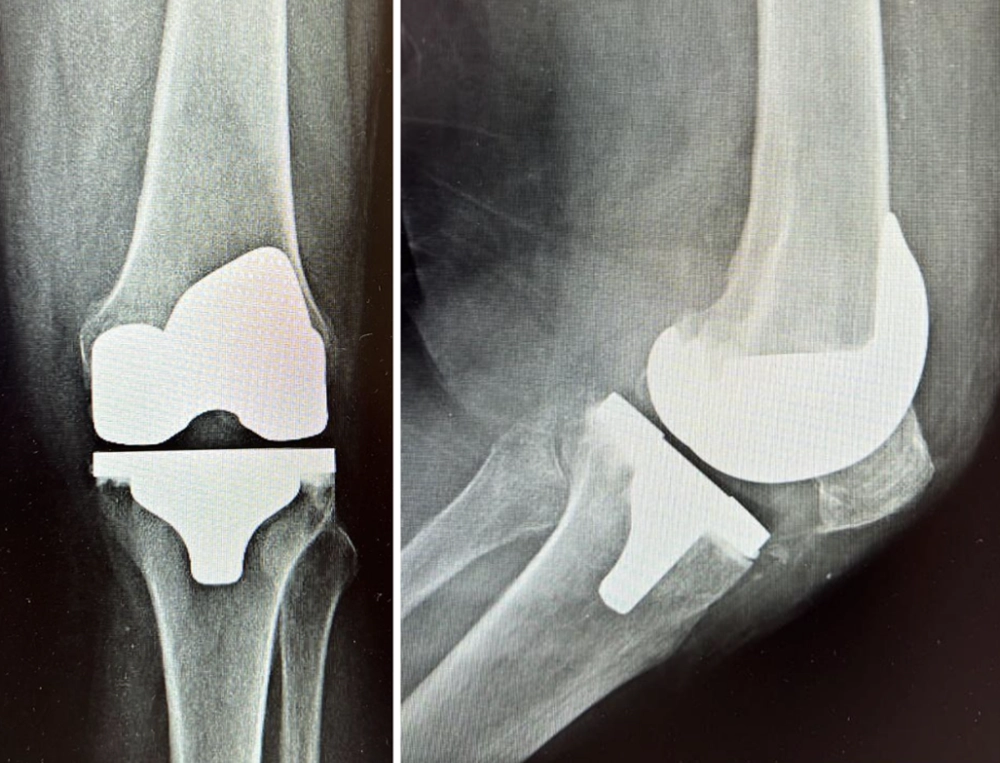

Na cirurgia de prótese toda articulação do joelho deve ser trocada?

Mito! Para os casos em que o paciente possui artrose em apenas uma parte do joelho, existe hoje a chamada prótese monocompartimental ou prótese unicompartimental na qual se substitui apenas o compartimento danificado preservando o restante dos compartimentos do joelho. Infelizmente em alguns casos após alguns anos é necessário converter para prótese total de joelho.